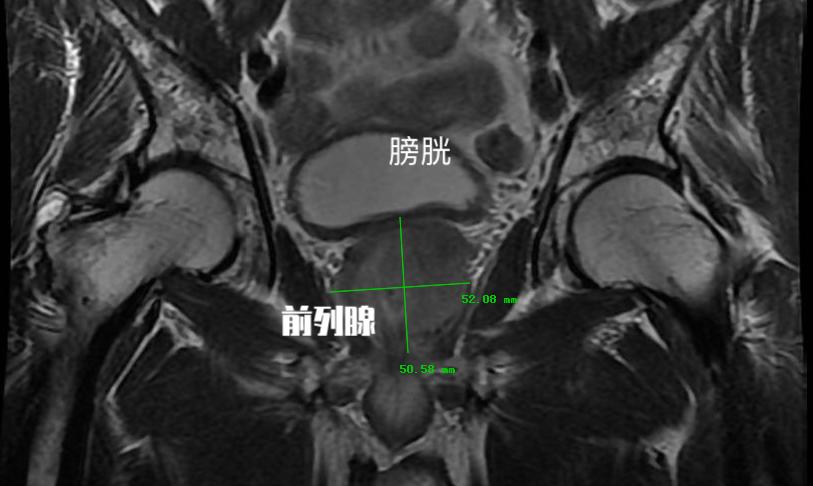

其实和临床我们确诊前列腺增生这个病有一些区别的地方在于 ,彩超给予患者前列腺增生这个诊断时候,是通过测量患者的前列腺体积。 超声检查可以了解 前列腺的形态、体积、有无异常回声、凸入膀胱的程度和残余尿量 。 前列腺体积的测量公式为0.52*前后径*左右径*上下径。

超声的诊断标准中, 如果测量的前列腺体积超过4cm*3cm*2cm时 ,在报告中就会描述为前列腺增生。因为患者的前列腺体积的确增大了。 而前列腺增生最主要的病理生理改变就是由于体积增大导致后尿道延长、受压变形、狭窄和尿道阻力增加。 这种前列腺体积增大就意味着从超声的角度可以诊断患者为前列腺增生。

同时彩超检查所反映出的前列腺体积增大, 并不是患者需要接受药物治疗或手术治疗的绝对指标。 现阶段临床评估前列腺增生临床进展的危险因素(感兴趣的可以看下之前文章)包括 年龄、血清PSA、前列腺体积、最大尿流率、残余尿量、症状评分、前列腺慢性炎、代谢综合征及膀胱内前列腺突入度。 前列腺体积只是威胁前列腺增生患者临床症状进展的一个临床指标。